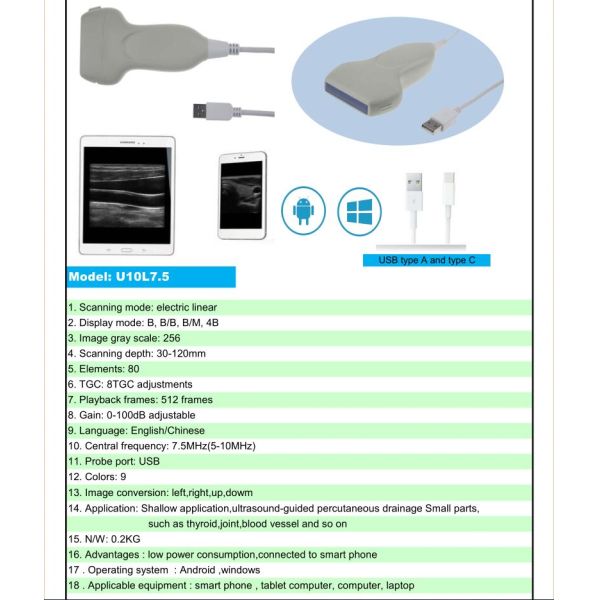

| Model | WCU01C3.5 | WCU01L7.5 |

| Type | Convex array probe | Linear array probe |

| scan mode | B, B/M, B+Color, B+PDI, B+PW | B, B/M, B+Color, B+PDI, B+PW |

| Frequency | 3.5/5.0MHz | 7.5/10MHz |

| Display Depth | 90~305mm | 20~100mm |

| Elements | 128 | 128 |

| Probe Radius | 60mm | / |

| Probe Length | / | 40mm |

| Wifi type | 2.4G/5G | 2.4G/5G |

| USB type | Type C | Type C |

| Image Adjust | B:GN(Bgain),D(depth), F(frequency),ENH(enhancement), TGC, DR(dynamicrange); Color/PW: GN,PRF,WF,Steer,Box; | B:GN(Bgain),D(depth), F(frequency),ENH(enhancement), TGC, DR(dynamicrange); Color/PW: GN,PRF,WF,Steer,Box; |

| Measure | B:Length,Area,Circumference,GA (CRL,BPD,GS,FL,HC,AC); B+M: Heart Rate, Time, Distance; B+PW: Velocity, Heart Rate(2), S/D; | B:Length,Area,Circumference,GA (CRL,BPD,GS,FL,HC,AC); B+M: Heart Rate, Time, Distance; B+PW: Velocity, Heart Rate(2), S/D; |

| Cinplay | Auto and manual, frames can set as 100/200/500/1000 | Auto and manual, frames can set as 100/200/500/1000 |

| Puncture assist function | in-plane puncture guide line, out-of-plane puncture guide line | in-plane puncture guide line, out-of-plane puncture guide line |

| Image/video Storage | Store on mobile phones,Tablet PC | Store on mobile phones,Tablet PC |

| Power | Built-in lithium battery, Replaceable | Built-in lithium battery, Replaceable |

| Standby | 1.5~4h according to scan mode | 1.5~4h according to scan mode |

| Charging mode | Usb | Usb |

| Bootup | Platform dependent, generally <5 seconds | Platform dependent, generally <5 seconds |

| Software | Android / iOS / Windows Download for free | Android / iOS / Windows Download for free |

| Standard Configuration | Host:1pcs, USB cable:1pcs | Host:1pcs, USB cable:1pcs |

| Dimensions | 115(h)x70(w)x20(d)mm | 115(h)x60(w)x20(d) mm |

| Package size | 185(w) *55(h) *105(d)mm | 185(w) *55(h) *105(d)mm |

| Net weight | 125g | 102g |

| Gross weight | 600g | 600g |